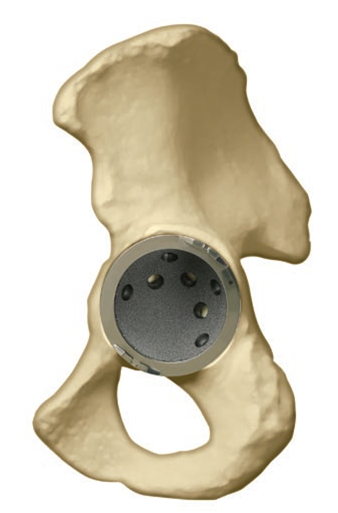

BHR Metal on Metal Acetabular Cup and Resurfacing Head - from http://www.rediscoveryourgo.com/Product.aspx?Product=BirminghamHip

• The BHR does not cause thighbone (femoral shaft) fractures as total hip replacement systems can.One-piece acetabular component versus two-piece acetabular component designs:

o The BHR acetabular component is provided in a one- and two-piece design.

o The potential benefits of the two-piece design for the patient include an option for additional fixation using bone screws, and an easier revision to a total hip replacement system if such replacement becomes necessary in the future. With the two-piece design, if the metal outer shell is well fixed, the surgeon has the option at a future revision surgery of leaving the metal outer shell in place without further disturbing the hip socket bone and replacing the metal liner with a plastic liner that can mate with a new total hip replacement system head and femoral

stem.

o The potential benefit of a one-piece design is that there is no risk of unintentional component disassembly.